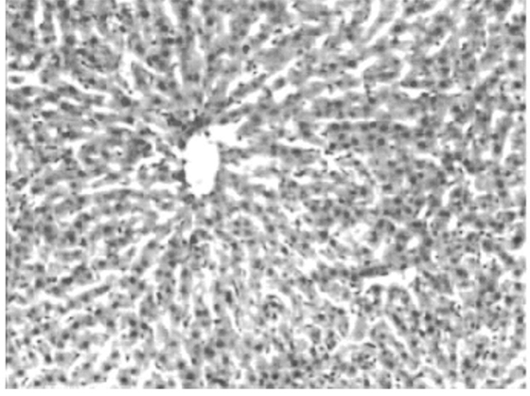

У крыс ОГ-1, в условиях индукции ишемии на фоне наркоза цитоангиоархитектоника печени была резко нарушена. Повсеместно дольчатое строение было нарушено. Гепатоциты теряли способность формировать белки, цитоплазма выглядела оптически светлой. В целом, во всех участках доминировали катаболические процессы, которые структурно выражались процессом вакуольной дистрофии (рис. 2а). В отдельных смежно расположенных гепатоцитах происходила резкая вакуолизация цитоплазмы, цитоплазматическая мембрана была фрагментро- вана, встречались признаки распада печеночных клеток, вплоть до появления очагов микронекроза (рис. 2б).

Рис. 2. Структурные сдвиги в печени подопытных животных, подвергнутых ишемии. ОГ-1. Гематоксилин- эозин.

а. Цитоангиоархитектоника печеночных долек резко нарушена. Гепатоциты теряют способность балочной ориентации и формировать характерные дольки. Картина диффузной вакуольной дистрофии. Об.10, ок. 10.

б.Деталь препарата а. Резкая вакуолизация цитоплазмы с признаками распада отдельных гепатоци- тов. Об. 40, ок. 10.